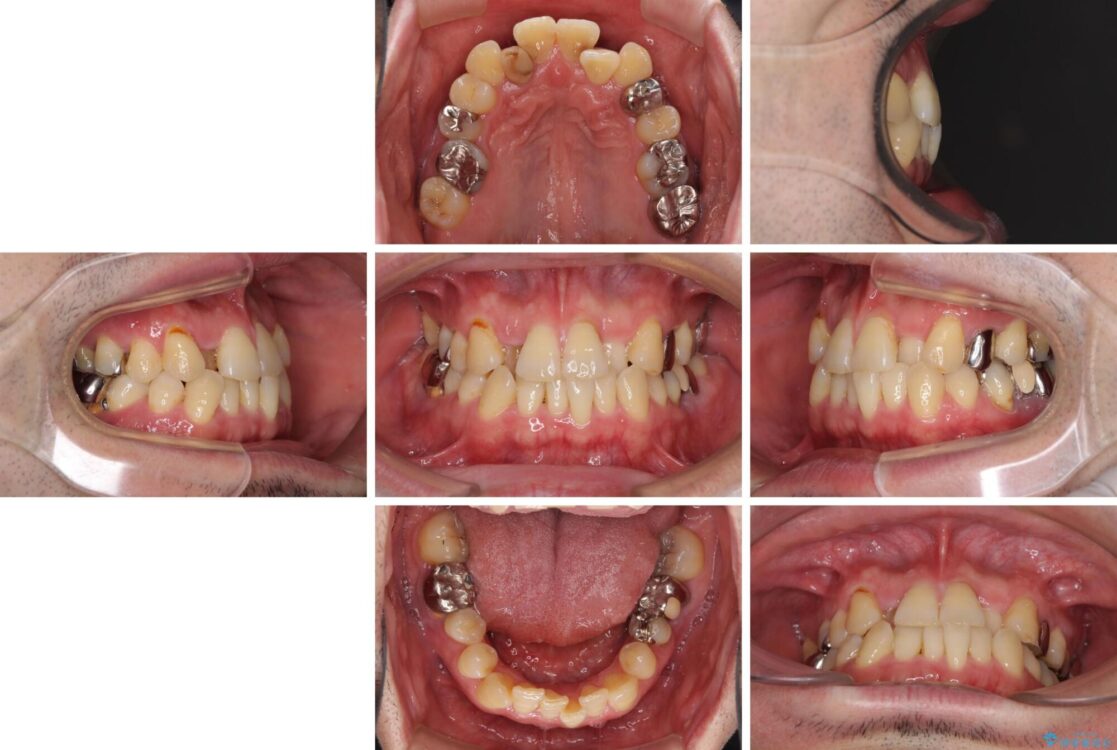

治療途中

• 割れてしまった奥歯とデコボコの前歯 矯正治療とインプラント治療 治療途中画像